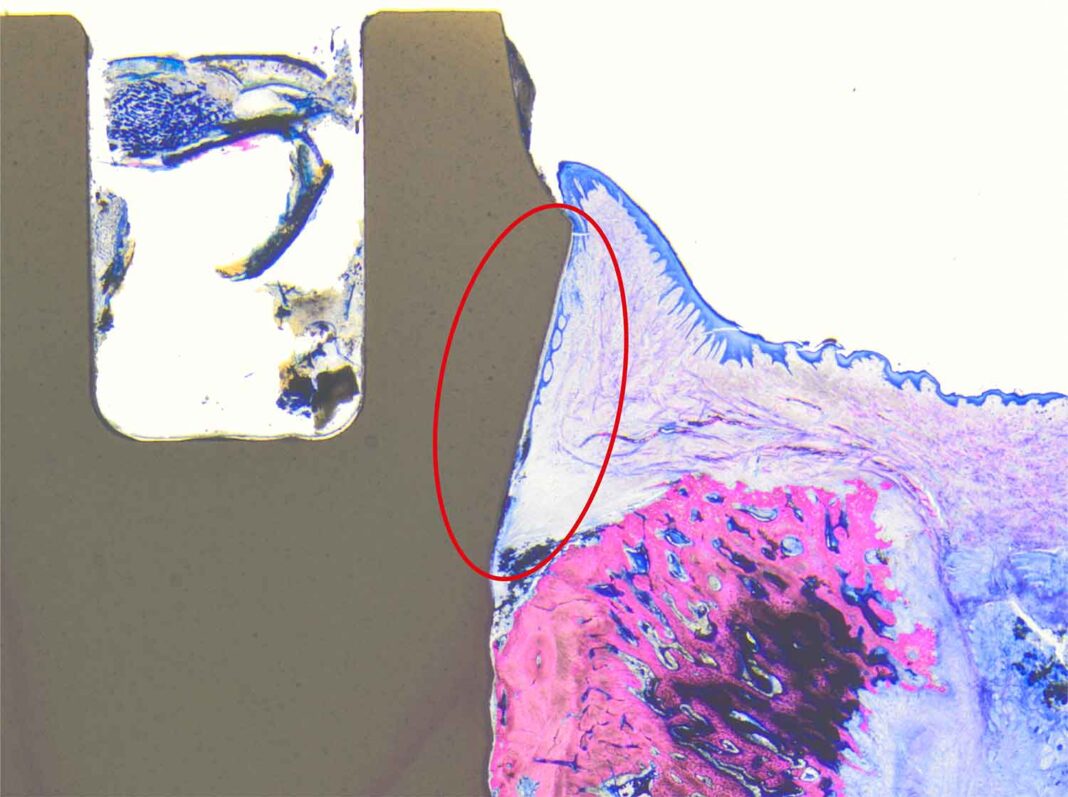

In histologischen Studien einer Schweizer Forschergruppe (Dr. Roland Glauser, Dr. Peter Schüpbach, Prof. Dr. Dieter Bosshardt und Prof. Dr. Dr. Anton Sculean) konnte kürzlich erstmals der Weichgewebsverbund bis auf das Pikometer-Level genau nachgewiesen werden. Die Forscher bestätigen, dass es bei Patent™ zu einem Verwachsen von Epithelzellen und transmukosaler Implantatoberfläche kommt.

Der für Patent™ Implantate spezifische Weichgewebsverbund wirkt als mukosale Schutzbarriere, welche die Abwärtsmigration von Plaque und das Eindringen von Bakterien in das periimplantäre Gewebe verhindern kann. Dadurch wird das Risiko von Gewebeentzündungen und Rezessionen drastisch reduziert und das Übergehen von Mukositis zur gefürchteten Periimplantitis verhindert. Zahnärzte haben dadurch erstmals die Möglichkeit, die Ästhetik ihrer Implantatversorgungen langfristig zu erhalten.